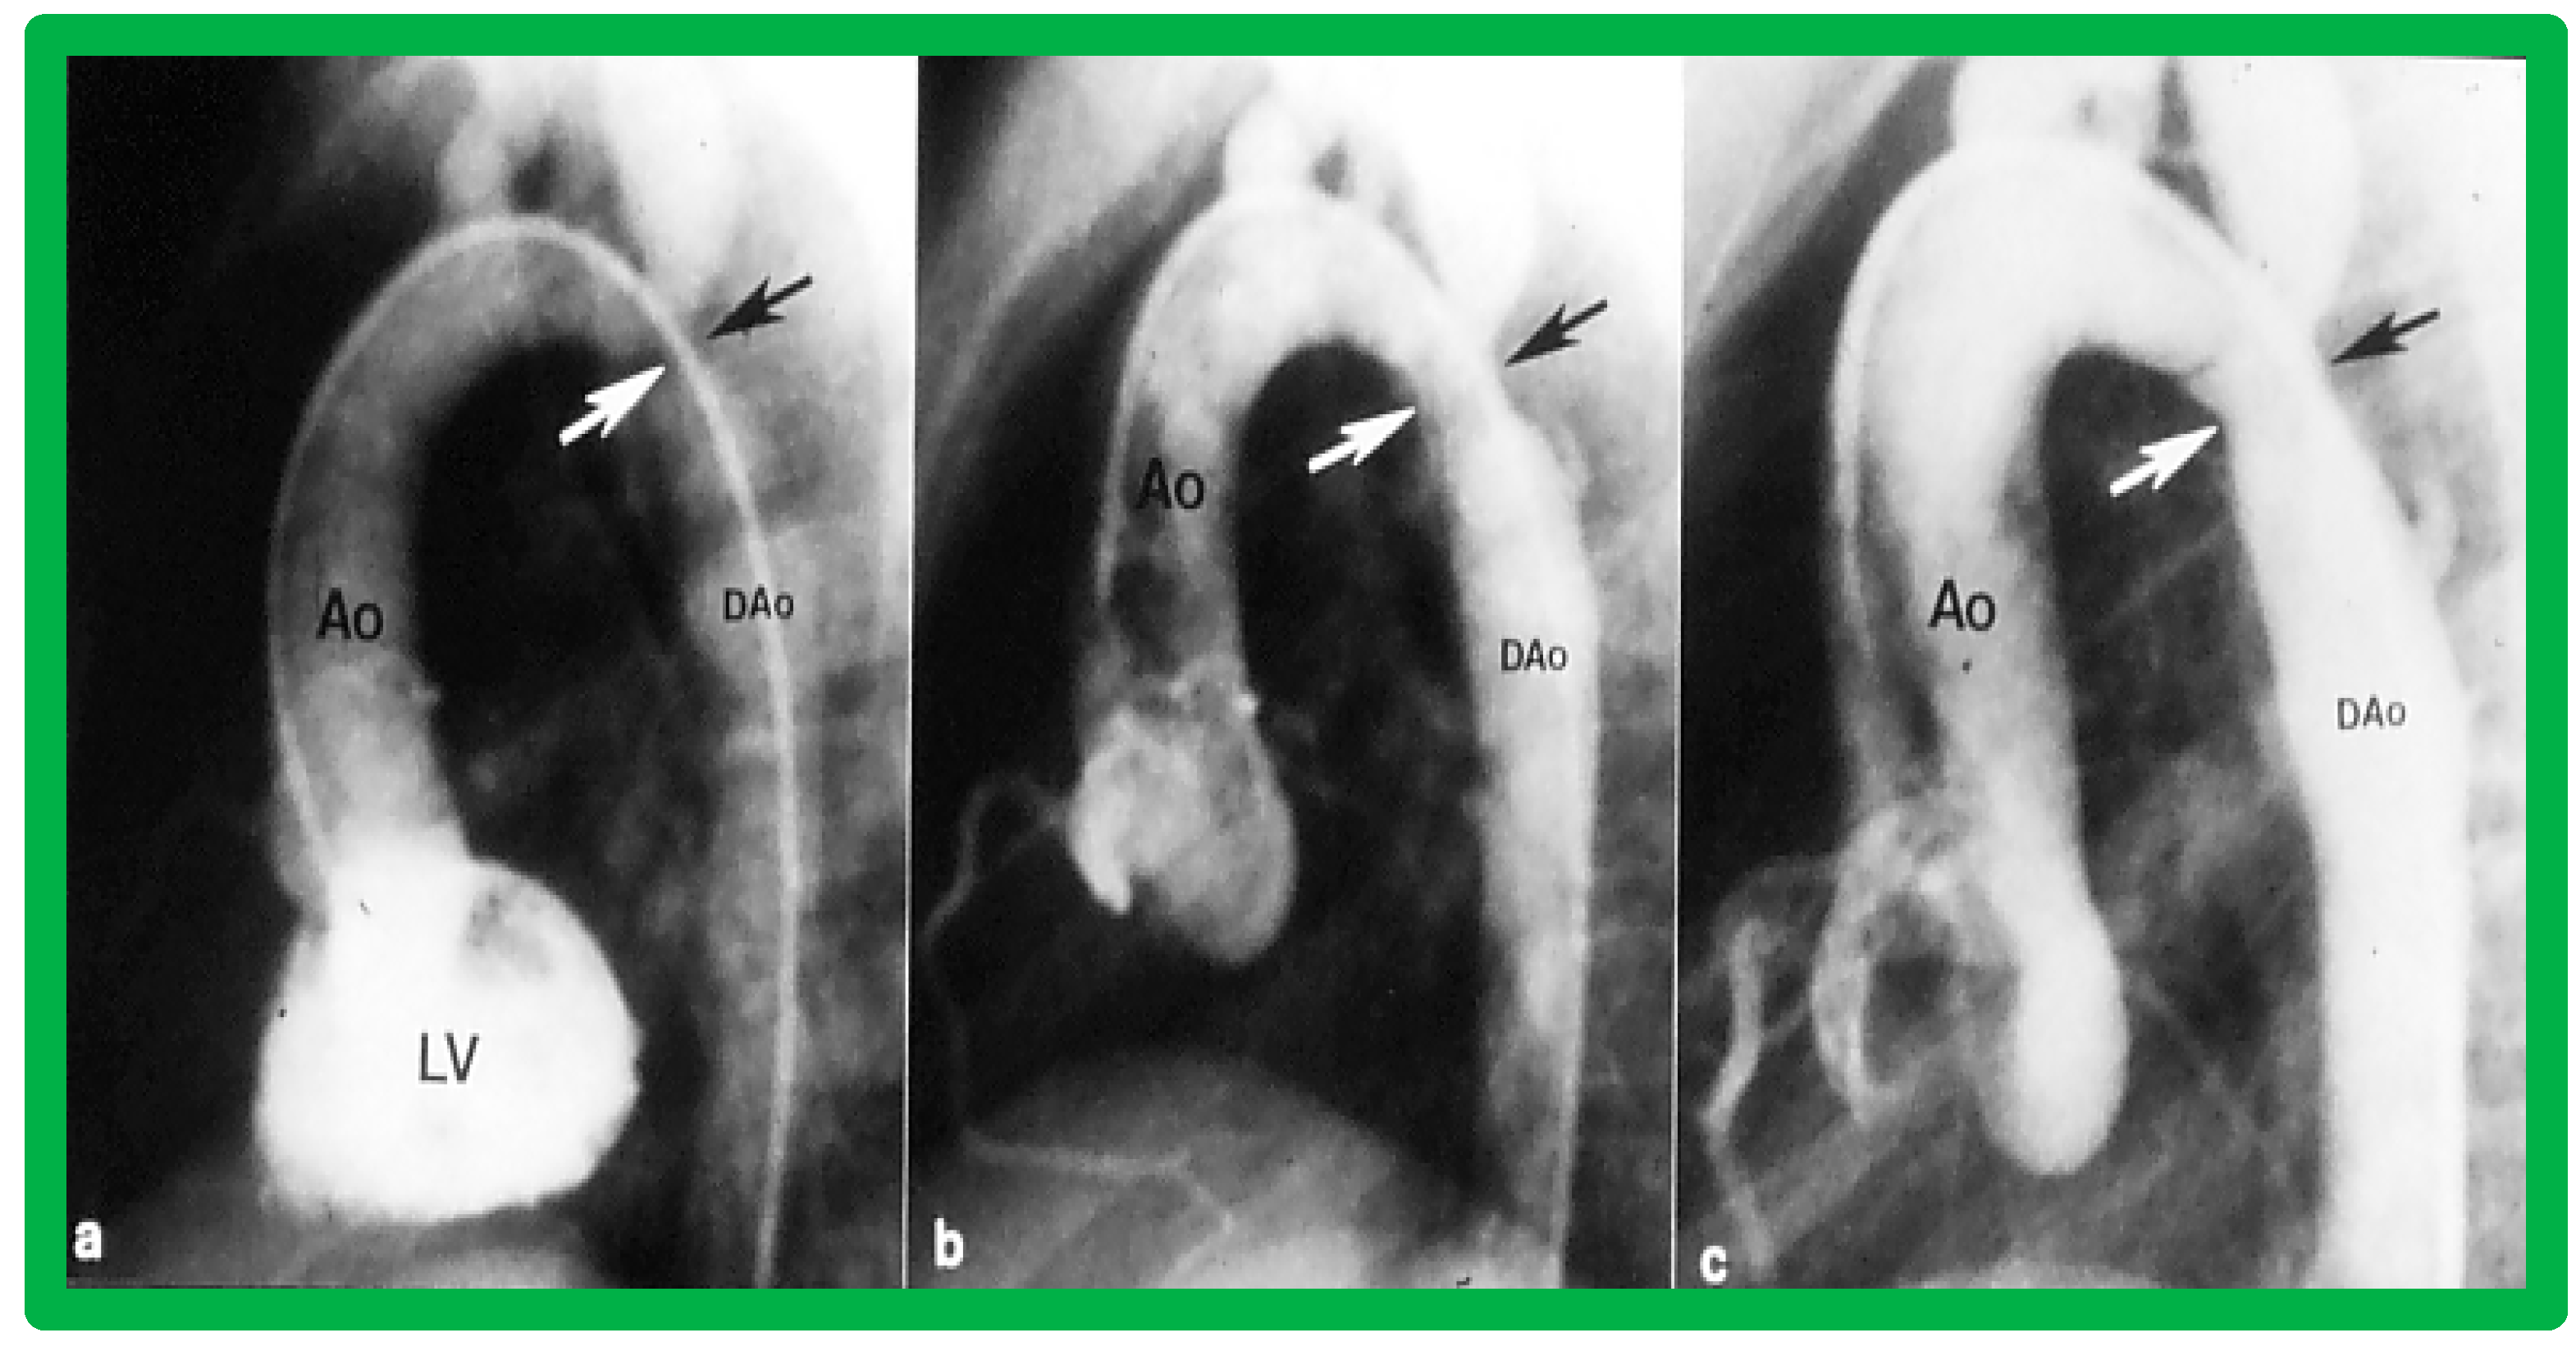

3.3. Aortic Coarctation, Native

4.3. Aortic Coarctation–Native

Revisit BA in the Neonate and Young Infant